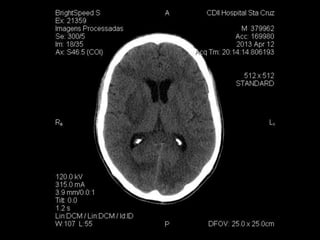

TC de crânio: lesões hipodensas esparsas em substância

branca, efeito de massa em região parietal esquerda.

Caso Clínico Hemograma: 6200leucócitos (B:4; S:60; L:25) Hb: 10 Ht: 30,9 Plaquetas: 210.000 Na: 136 K: 4,29 Uréia: 51 Creatinina: 0,85 HIV + TC de crânio: lesões hipodensas esparsas em substância branca, efeito de massa em região parietal esquerda. HD: Neurotoxoplamose ou linfoma? Paciente internado para investigação.